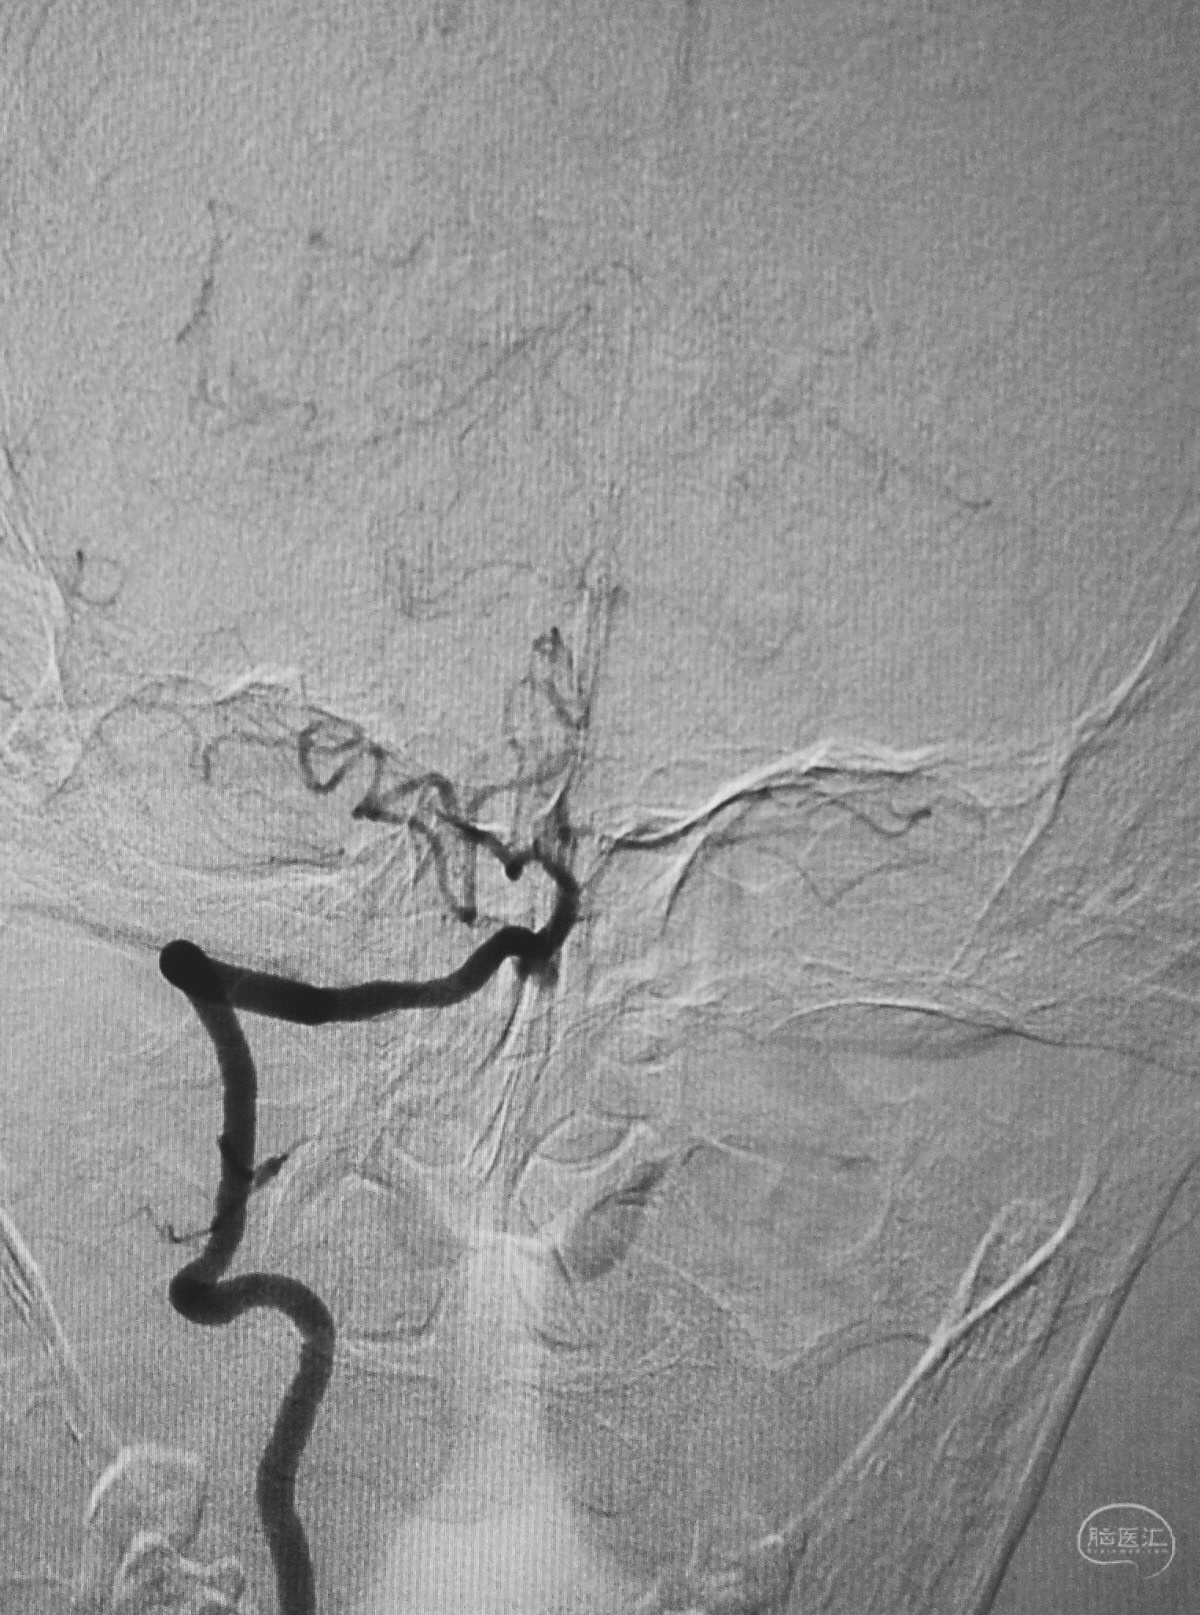

Echelon 10微导管头无论塑成C形还是S形,均无法稳定于动脉瘤腔内,遂使用回马枪技术,使微导管成襻通过,管头折返入瘤腔。

跨瘤颈释放Solitaire 4×20支架(蓝线),压住微导管(红线),在支架保护下经返折的微导管送入弹簧圈填塞瘤腔。

依次送入QC-2-4-3D,2-3-Helix,1.5-2-Helix,1.5-2-Helix四枚弹簧圈,最后一枚弹簧圈将管头(箭头)顶出瘤腔。

将Traxcess 14微导丝送入微导管,稍向远心端送微导管,使管头远离动脉瘤,再缓慢撤离。

解脱第一枚Solitaire 4×20支架后,套叠置入第二枚Solitaire 4×20支架,置入两枚支架的原因是考虑该瘤是夹层动脉瘤,多支架能够强化血流导向作用,有利于夹层愈合。

术后右椎动脉工作位造影,

以及正位造影显示动脉瘤完全栓塞,载瘤动脉畅通。